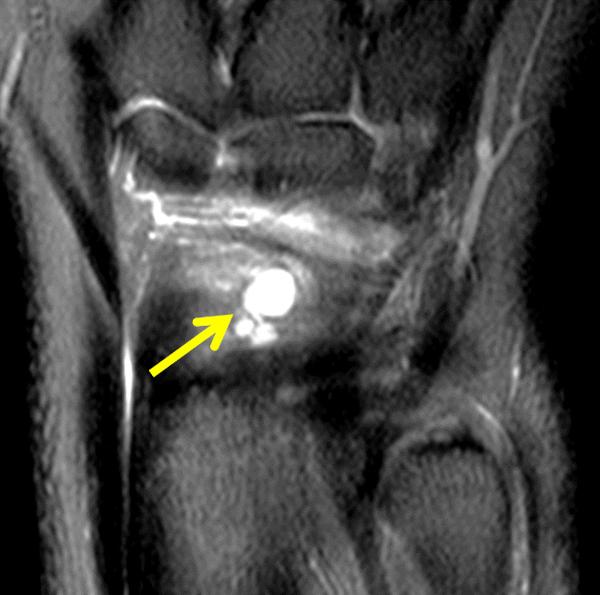

Mucous Cyst Raleigh Hand Surgery — Joseph J. Schreiber, MD

Wrist Ganglion Cysts Radsource What Does A Cyst Look Like On Xray Some types of cysts have the potential to become cancerous. A cyst is a pouch within tissue that contains fluid, air, or other materials, while a tumor is an irregular growth of tissue that is not typical for the area. Cysts are closed sacs found within the body and are common on the skin. Find out more about why cysts. What Does A Cyst Look Like On Xray.

From www.schreibermd.com

Mucous Cyst Raleigh Hand Surgery — Joseph J. Schreiber, MD What Does A Cyst Look Like On Xray Find out more about why cysts form and. A cyst is a small sac filled with air, fluid, or other material. A tumour is an unusual area of extra tissue. Both can be found in your skin, tissue, organs, and bones. These small sacs filled with fluid, tissue, hair, or dead skin can form almost anywhere on your body. The. What Does A Cyst Look Like On Xray.